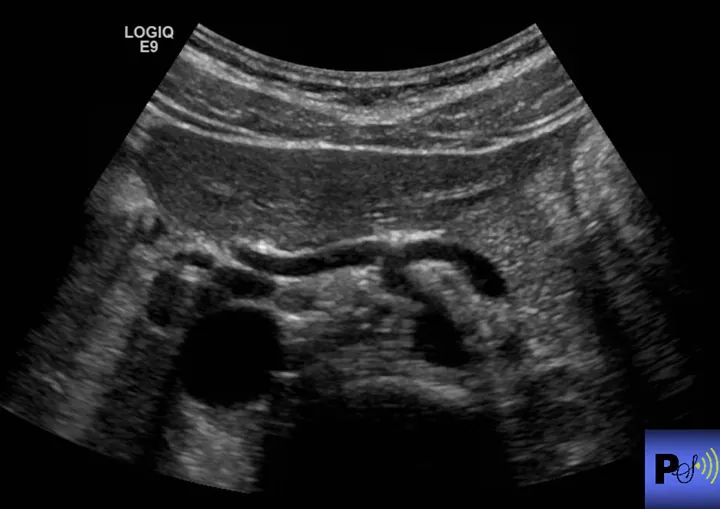

What is the name of this sign? What structures are involved?

Exclamation point sign.

Gallbladder, portal vein, liver, IVC.